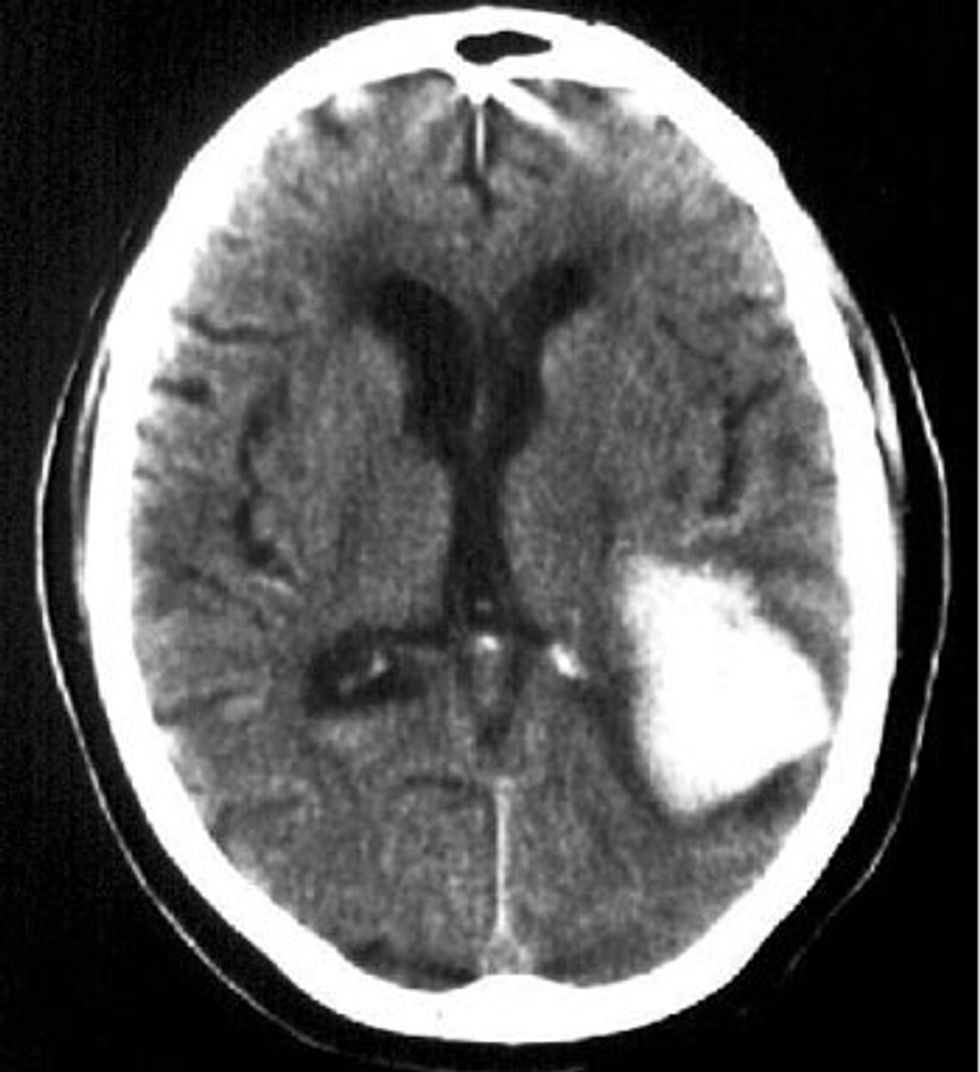

CT endocraniumi ku shihet hematoma intracerebrale parietale e majtë që komprimon cornu occipitalis të ventrikulit lateral. Gjithashtu shihet fillim i një hydrocephali obstruktive treventrikulare